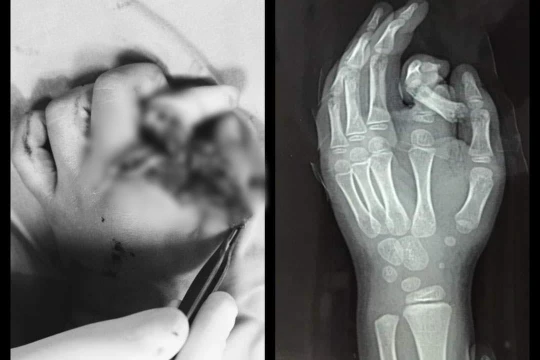

VietTimes – Trong lúc chơi đùa ở nhà, bé trai cho tay vào máy giặt đang hoạt động. Chỉ vì một phút nghịch dại, ngón tay của bé đã bị đứt lìa, hệ thống thần kinh dây chằng bị nhổ bật cả đoạn dài .